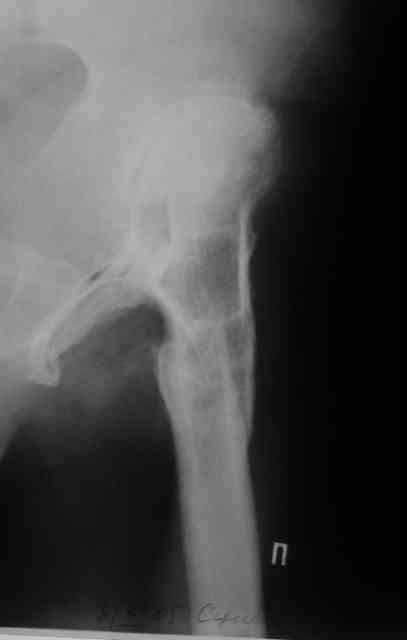

В прищепке случай 1999 года - эндопротезирование после операции Шанца-Илизарова. Возраст пациентки 45. Коррекция была в 17 лет. А Рыков Хабаровск.